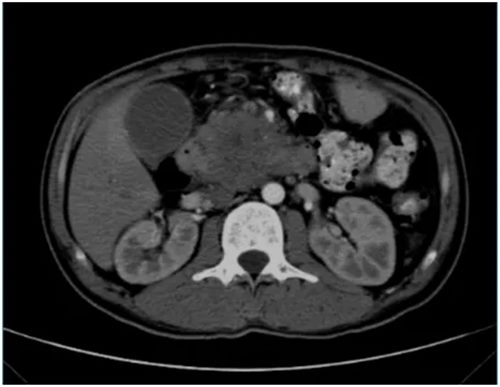

初到医院时,小陈的病情确实棘手。入院CT、MRI提示:胰头颈部胰腺癌并周围侵犯;肿瘤已经包绕侵犯了几支重要血管:门静脉主干、脾静脉、胃左动脉、肠系膜上动静脉、下腔静脉,并且可见病灶周围及肠系膜根部多发淋巴结。陈艳军主任仔细评估后,制定了“先调整,后消融”的策略:先行全身化疗联合免疫治疗,争取控制肿瘤发展,为后续治疗创造可能。

在团队的精心治疗与呵护下,奇迹出现了。多次行化疗和免疫治疗后,复查CT显示肿瘤明显缩小!时机成熟,陈主任当机立断:可以行纳米刀消融术!